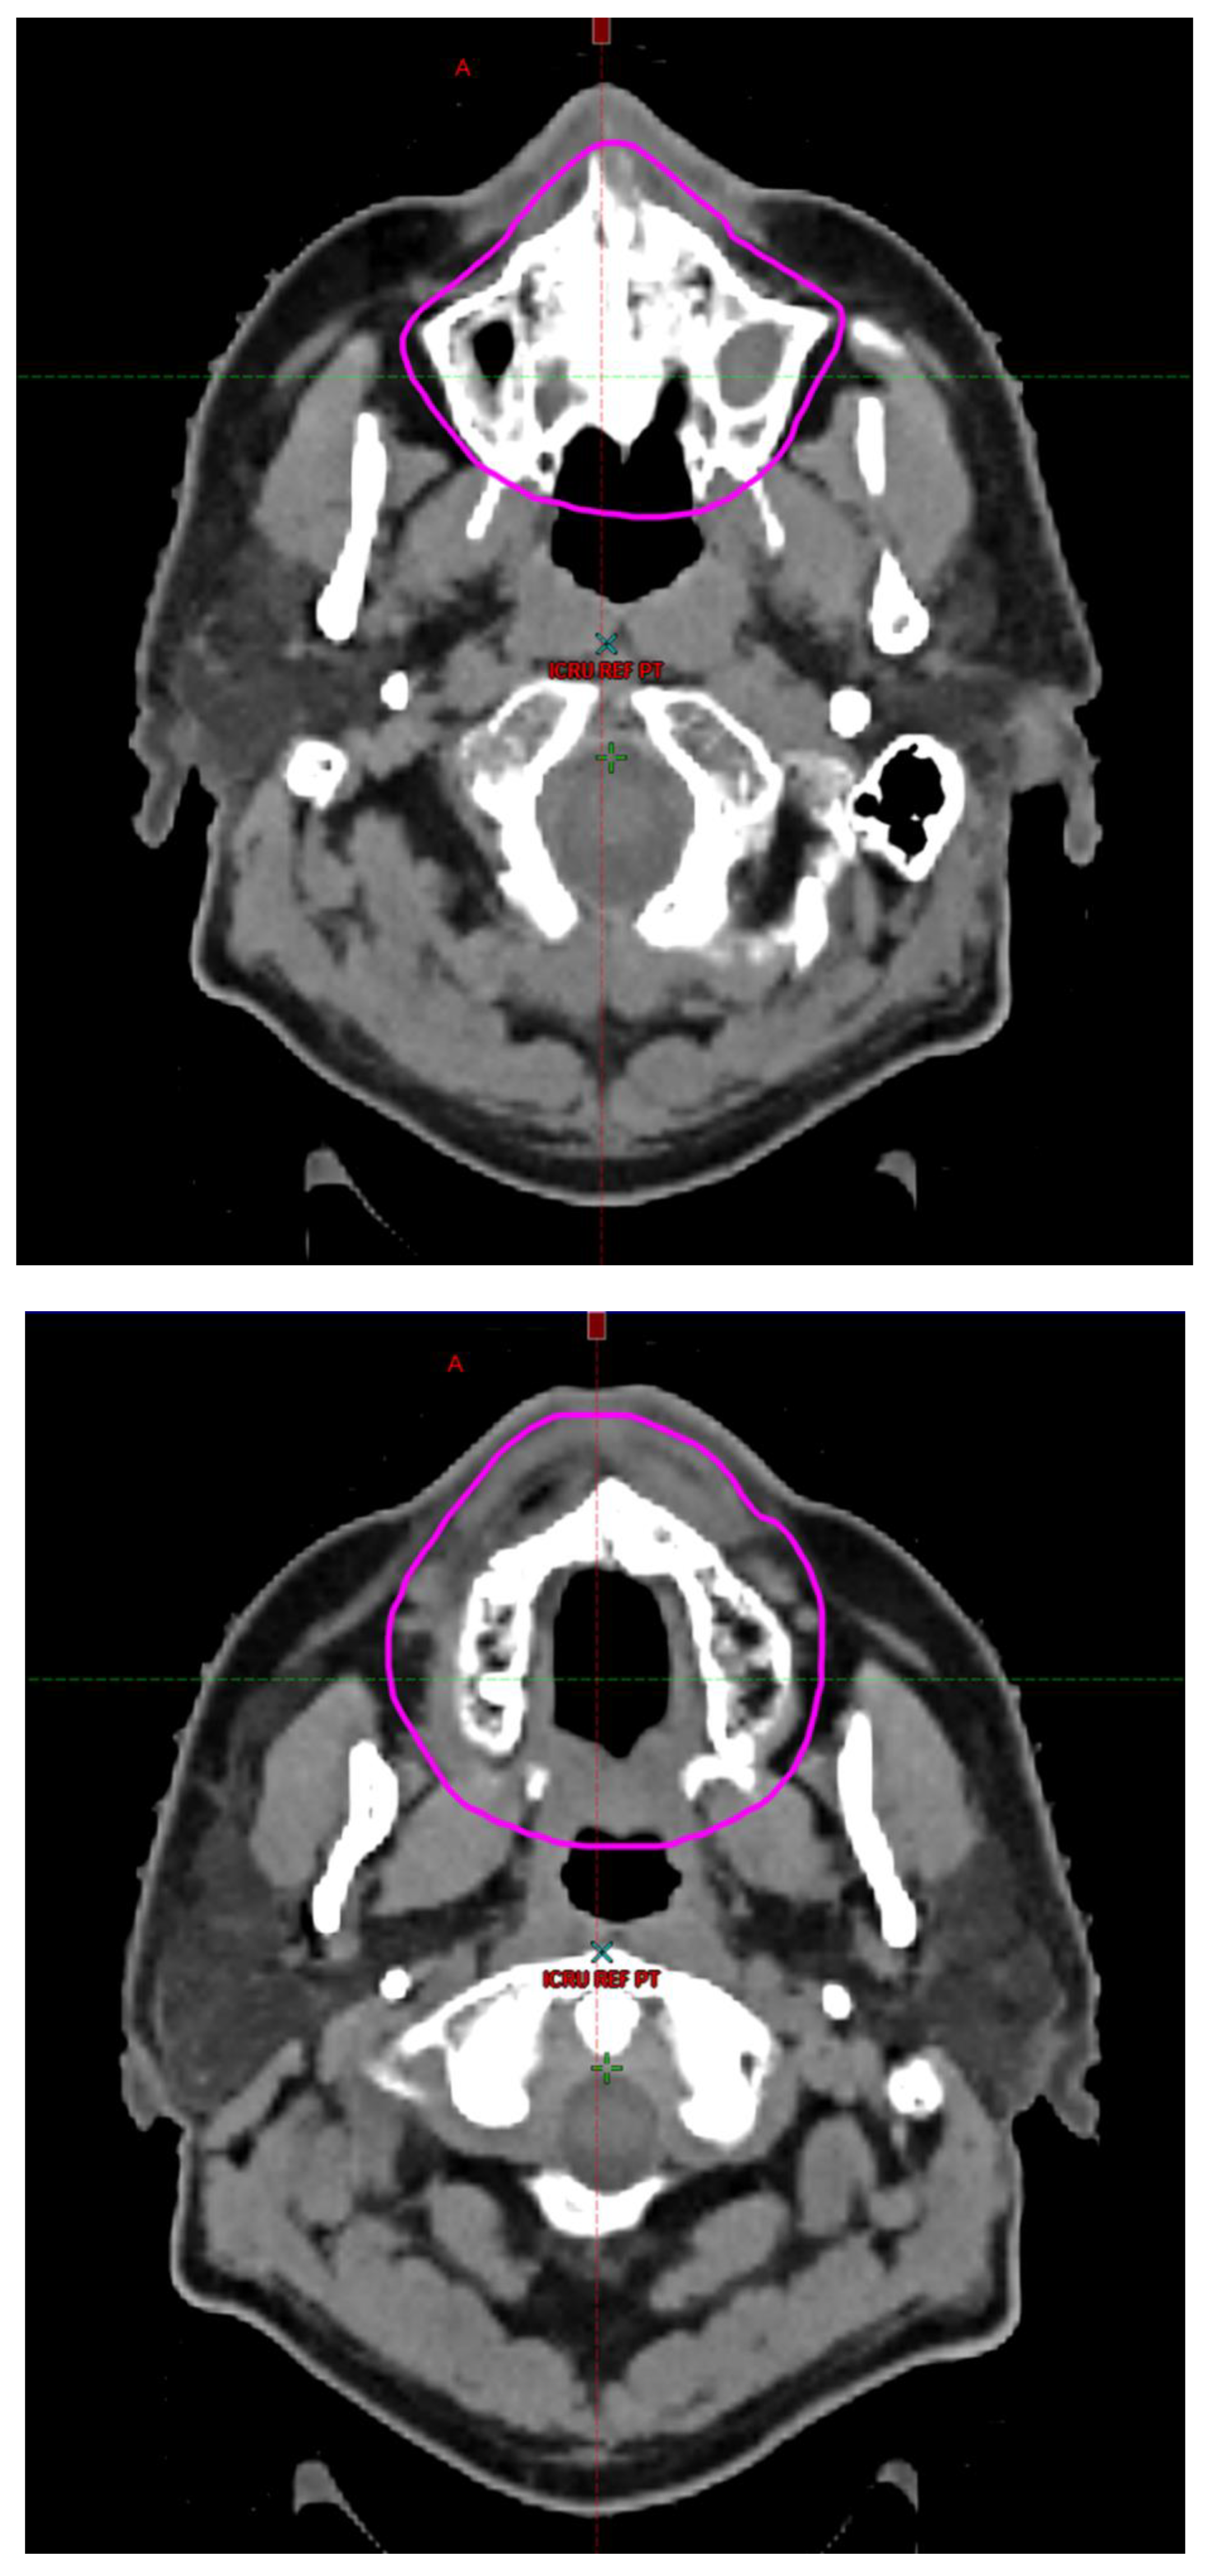

Radiotherapy treatment plans were created, and dose volume histograms (DVH) were generated using the Eclipse treatment planning system (Varian Medical Systems, Palo Alto, CA). The standard photon treatment plans consisted of three volumetric modulated arc therapy fields. The standard proton treatment plans consisted of three to four fields with the pencil beam scanning technique. For proton therapy plans, the RT dose was scaled by 1.1 to account for the difference in relative biological effect when compared to conventional photon treatments. A definition for oral cavity OAR avoidance structure evolved at our institution between 2003 and 2016 when it was formalized and accepted as the consensus standard for treatment planning (Figure 2). The DVH statistics for the oral cavity OAR, and the mean dose to the left and right submandibular glands, left and right parotid glands and total parotid glands were calculated and extracted. Pharyngeal constrictor, intrinsic and extrinsic muscles of the tongue, and laryngeal DVH statistics were not included since swallowing function is not a primary endpoint for this study. There were four patients who did not complete the planned course of treatment. In these cases, the prescribed dose was scaled to the delivered dose.

The superior extent of the oral cavity OAR avoidance structure includes all the mucosa of the hard palate. The contouring of the OAR begins superiorly at the first sign of mucosa on the alveolar ridge of the maxilla (medial and lateral) and hard palate. It then continues inferiorly to include the mucosa of the upper and lower lip, mucosa of the hard and soft palate including the uvula, the buccal mucosa including the buccinator muscles, the mucosa of the retromolar trigone, the entire tongue (anterior two-thirds, dorsal surface and tongue base), floor of mouth, sublingual glands, gingival mucosa of the mandible (lingual and buccal surfaces), and ending at the level of the cranial edge of the hyoid bone and caudal edge of the mandible. It also includes the maxillary and mandibular teeth if present. The posterior extent includes the soft palate, uvula, and tongue base. The anterior extent includes the mucosal surface of the posterior one-half of the lips and the gingival mucosa of the maxillary and mandibular alveolar ridges and retromolar trigone. The lateral extent includes the buccal mucosa and buccinator muscles. The oral cavity OAR contains most of the taste buds which are located within the mucosa of the anterior two-thirds of the tongue, the floor of mouth, the buccal mucosa, the lips, the pharynx (including the soft palate, uvula, and base of tongue), the larynx (epiglottis) and upper third of the esophagus [4]. The oral cavity OAR also contains the minor salivary glands located within buccal, labial, lingual, soft palate, lateral parts of the hard palate, and floor of the mouth submucosa and in the trough circling the circumvallate papillae on the dorsal surface of the tongue near the terminal sulcus [3]. Therefore, the oral cavity OAR for radiotherapy (RT) treatment planning purposes is defined as including the anterior two-thirds of the tongue, floor of mouth, buccal mucosa, mucosal surface of the lips, soft palate, uvula, base of tongue, hard palate and circumvallate papillae on the dorsal surface of the tongue. The gingival mucosa of the alveolar ridges of the mandible and maxilla and the mucosa of the retromolar trigone are also included in the definition to further reduce the incidence and severity of painful oral mucositis. Finally, the sublingual glands are included in the oral cavity OAR structure. The larynx (epiglottis) and upper third of the esophagus are not included in this OAR volume because they are included in their own OAR avoidance structure (larynx, cricopharyngeal inlet, cervical esophagus).

Figure 2. Oral Cavity Organ at Risk (OAR) Avoidance Structure Definition.

Preprints 93045 g002aPreprints 93045 g002bPreprints 93045 g002cPreprints 93045 g002d